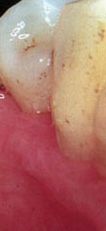

pase el ratón sobre las piezas para ver: bolsa, recesión y movilidad